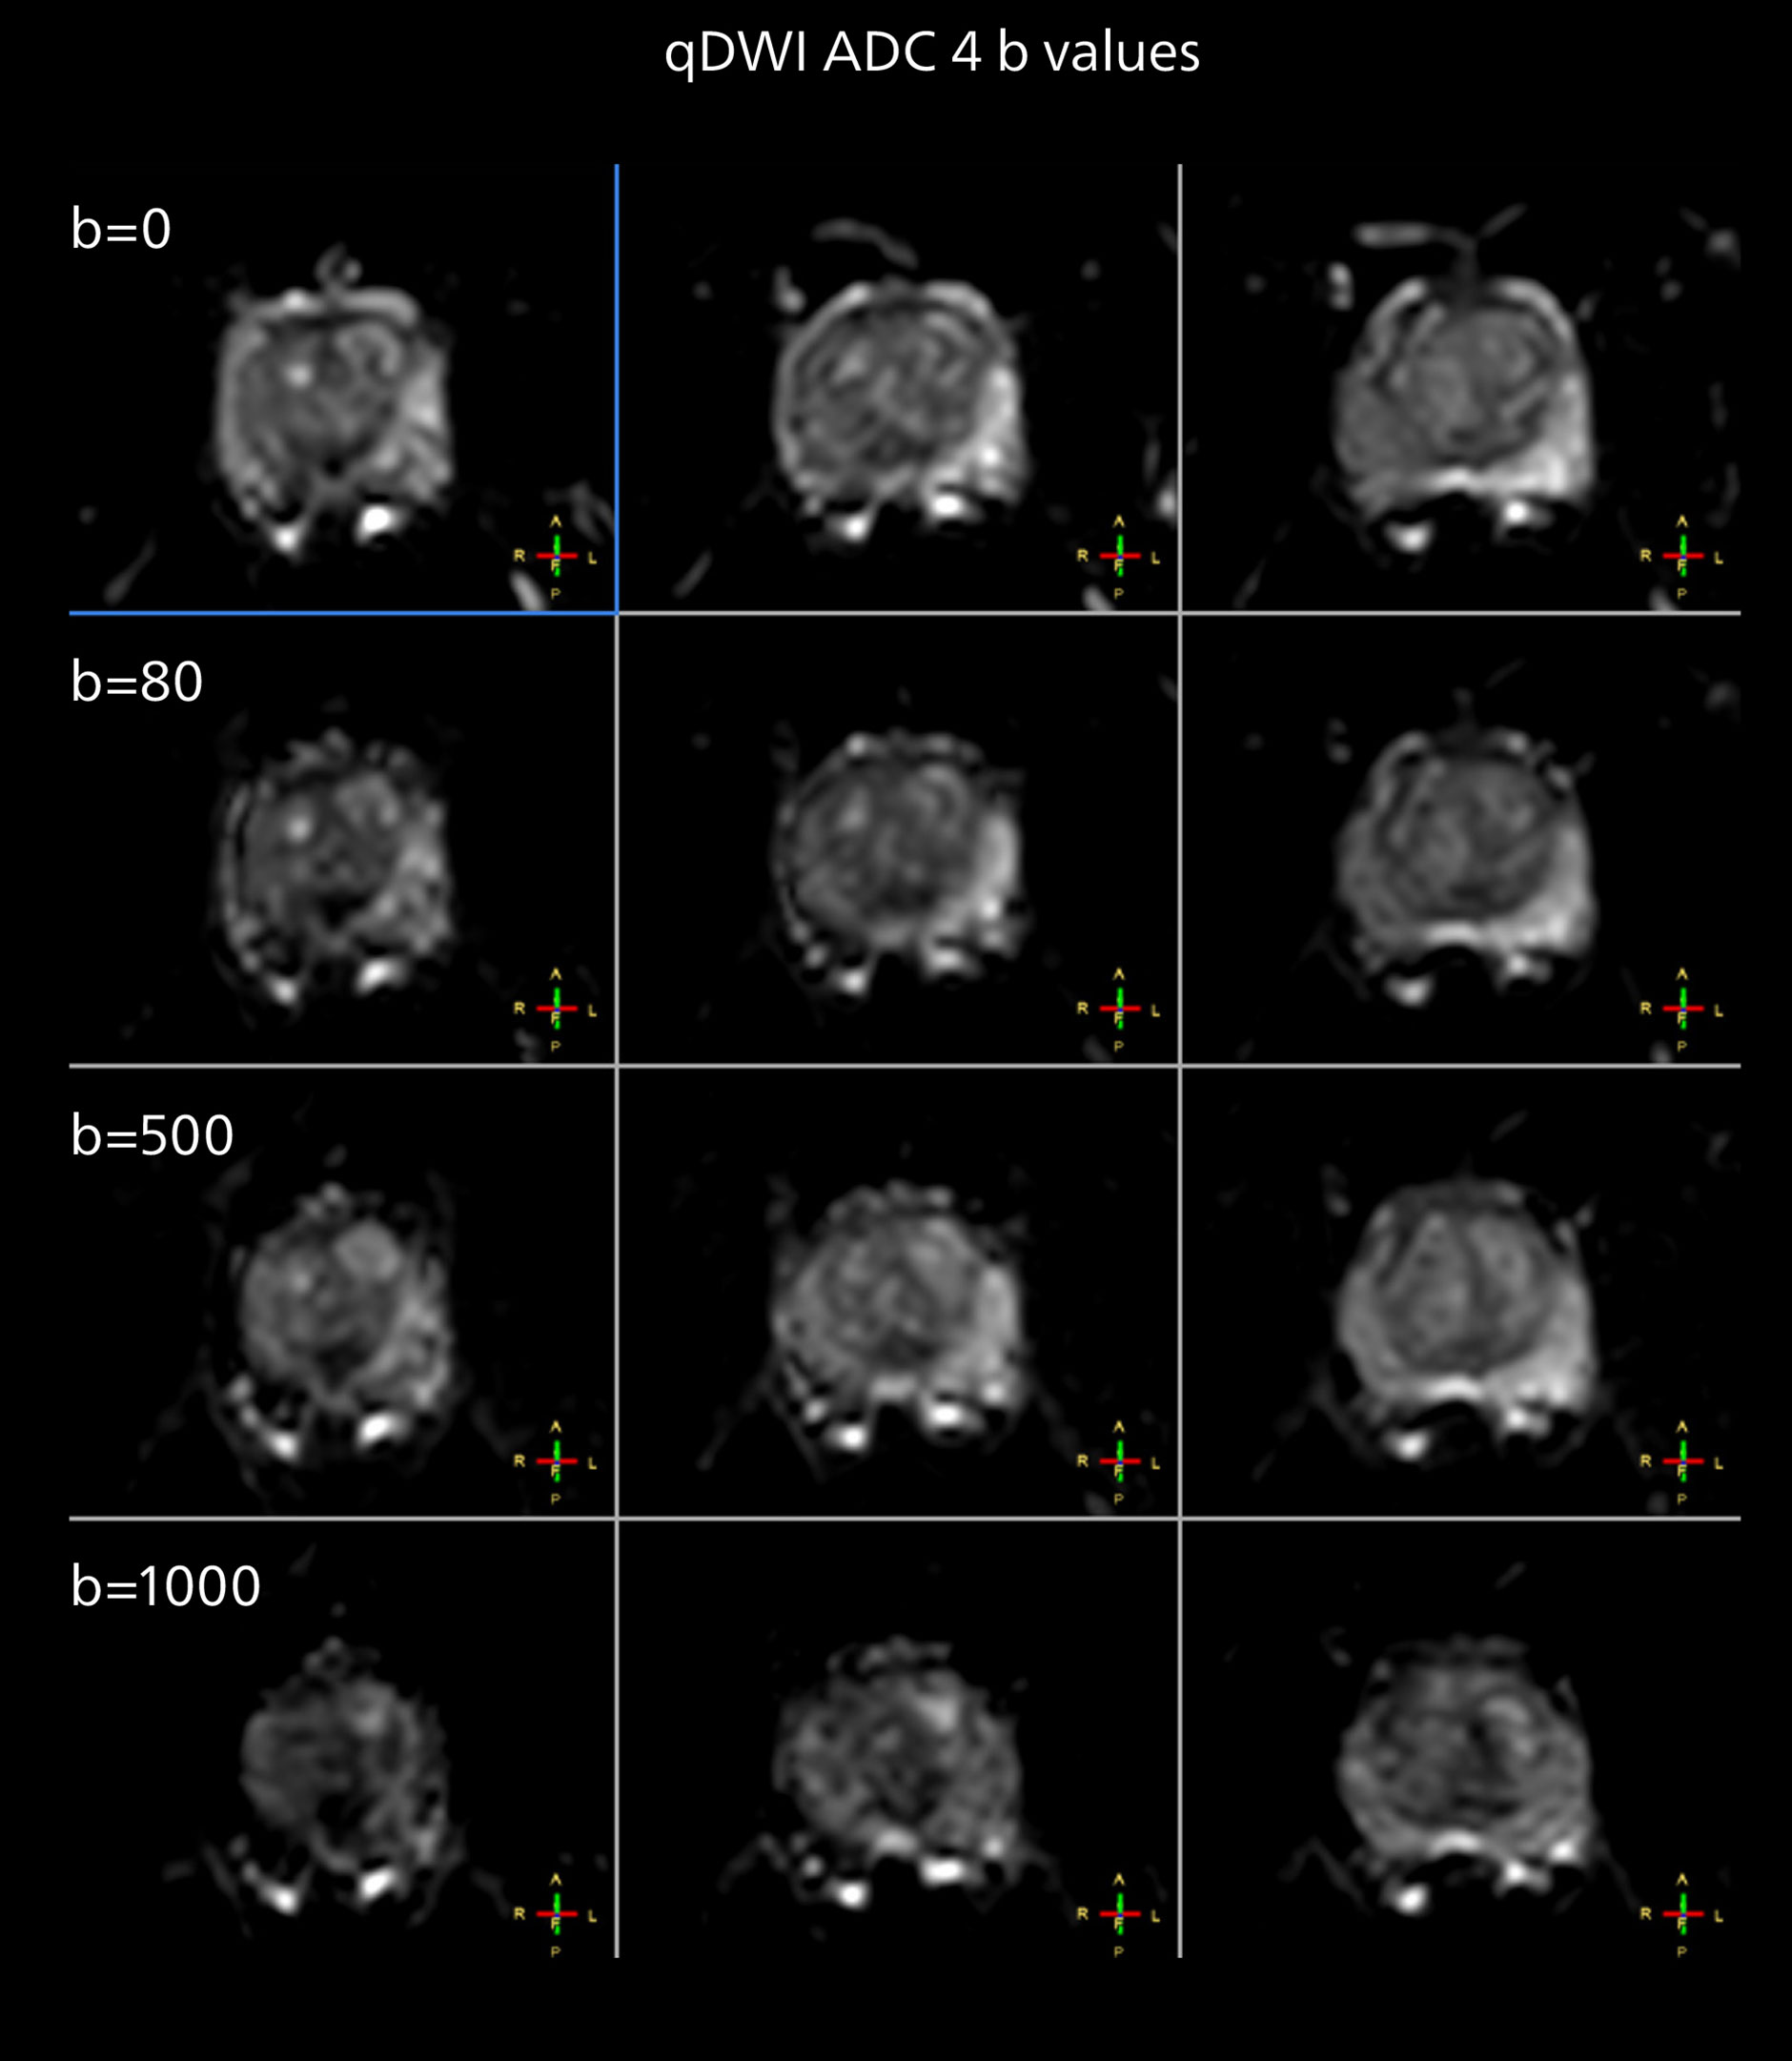

Diffusion weighted imaging of prostate

The examples on the left show the regular clinical diffusion protocol with four b-values up to b1000 s/mm². On the right, the T2W image shows a hypointense lesion that has low ADC and is clearly visible in b1400 and b2000 diffusion images, suggesting malignancy.

The prostate DWI done so far with the MR 7700 looks promising; the quality of visualizing the gland and the areas of disease seems significantly improved. “In one of our first prostate patients we were already able to acquire a quite high-resolution diffusion image – using a b-value of 3000 – that clearly delineated the prostate lesion. That was a very nice example of what the MR 7700 gradients can achieve,” he says.